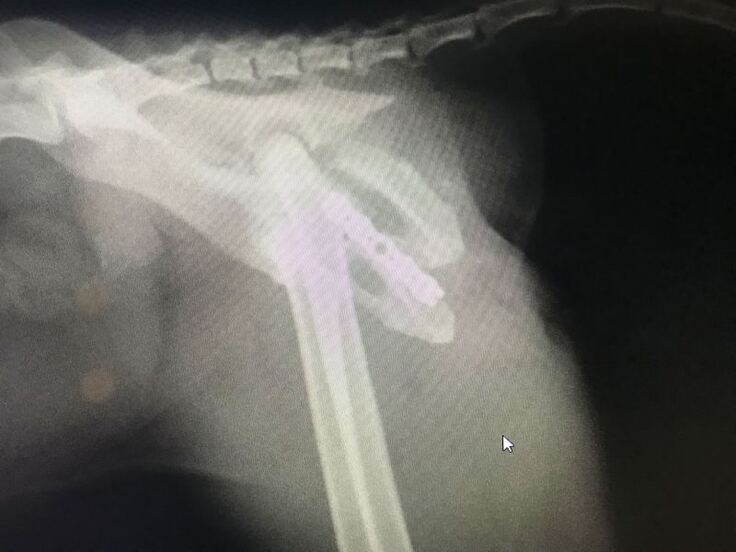

脚が立たないようなので仔猫2匹とクロちゃんを一緒に保護して動物病院で診察してもらうと、骨盤骨折していました。

初診のレントゲンでは骨盤の左側が骨折という診断で手術を受けましたが、手術後のレントゲンで右側も骨折していて、粉砕骨折しているという結果でした。

交通事故に遭ったのだと思いますが、骨盤骨折して立てない動かない脚を前脚だけで引き摺って仔猫の元に帰ろうともがいて頑張って家の前まで帰って来ていたクロちゃん、なんとかうまく骨がつながって普通に歩いて走ってジャンプできるようになって欲しいと思います。

骨盤骨折しても必死で仔猫の元に帰えろうとしていたクロちゃんの骨盤骨折(粉砕骨折)を手術して元のように歩いて走ってできるようにしてやりたい。